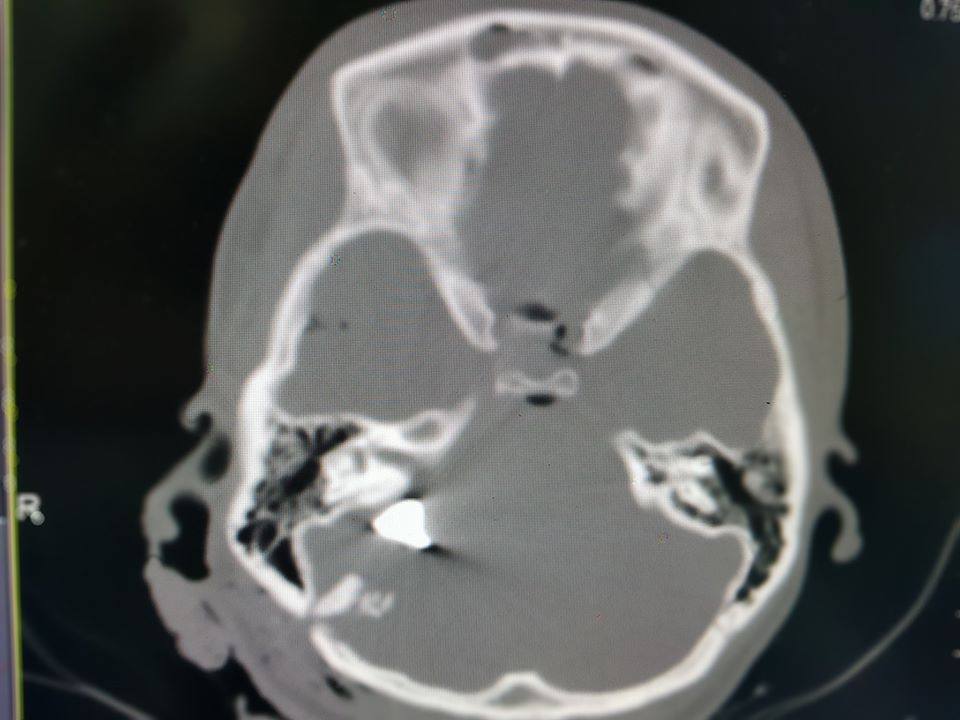

"Крайне тяжелое состояние, кома III степени, искусственная вентиляция легких и сверхвысокие дозы препаратов, поддерживающих артериальное давление. Взрывная черепно-мозговая травма, перелом костей свода и основания черепа, металлические обломки повредили жизненно важные участки мозга. Травма, не совместима с жизнью", - написал Толубаев.